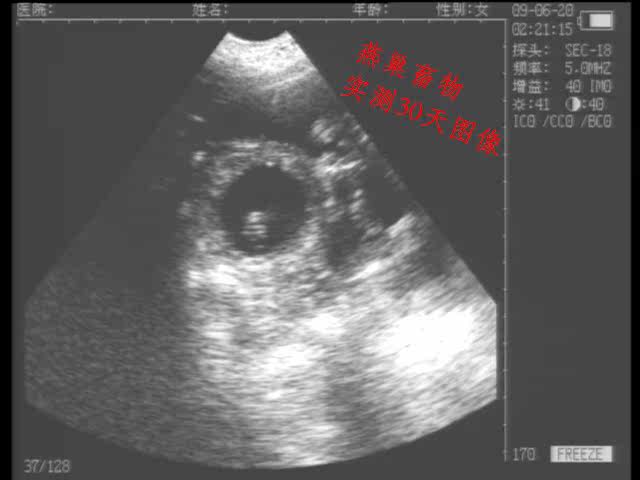

适用于猪等动物怀孕诊断

高性价比,能出色的胜任猪场等的怀孕检测等工作。

探 头:3.5MHz防水机械扇扫(可选配5.0MHZ防水机械扇扫)

独特的小型防水机械扇扫探头,既可作为常规体外探头,也可作为直肠探头使用

探头频率可调节,应用范围更广